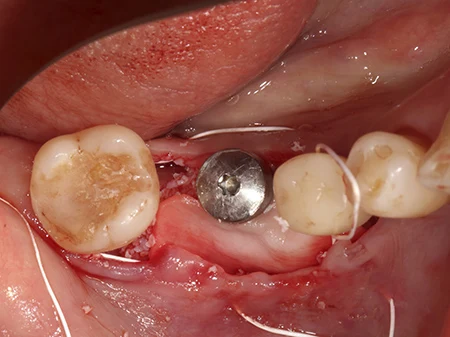

歯ぐきを切開し開いた状態。骨が前後の歯に比べて細いのがわかります。

インプラントを埋入した状態。骨の外側からインプラントの一部がはみ出しています。